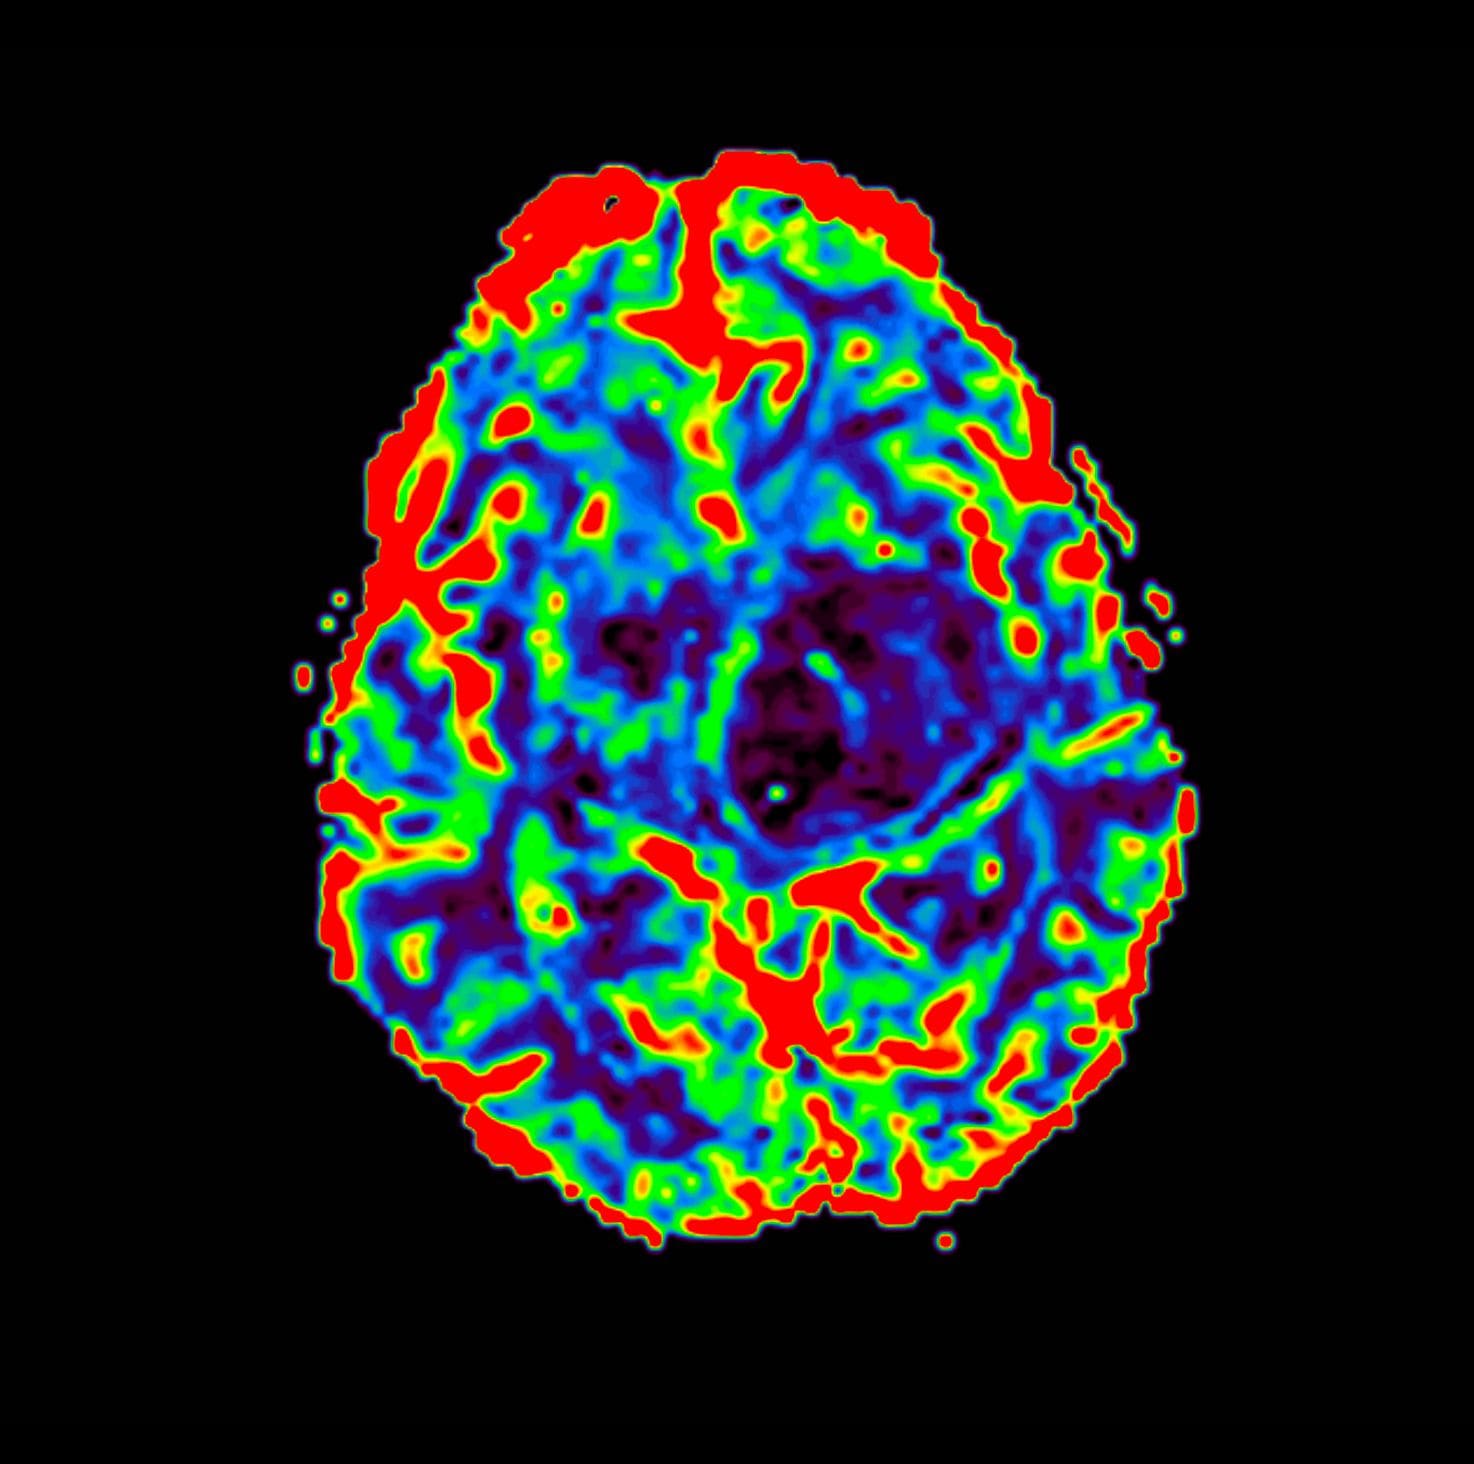

EVAA Radiology provides comprehensive teleradiology services across all subspecialties, with a commitment to excellence and a personal touch—ensuring that referring doctors always have access to a radiologist for discussion whenever needed.

At EVAA Radiology we provide tele-radiology services in the following subspecialties –